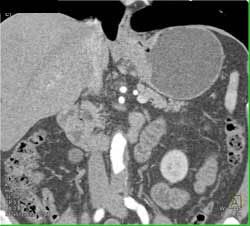

Drainage of A Pseudocyst Into the Stomach